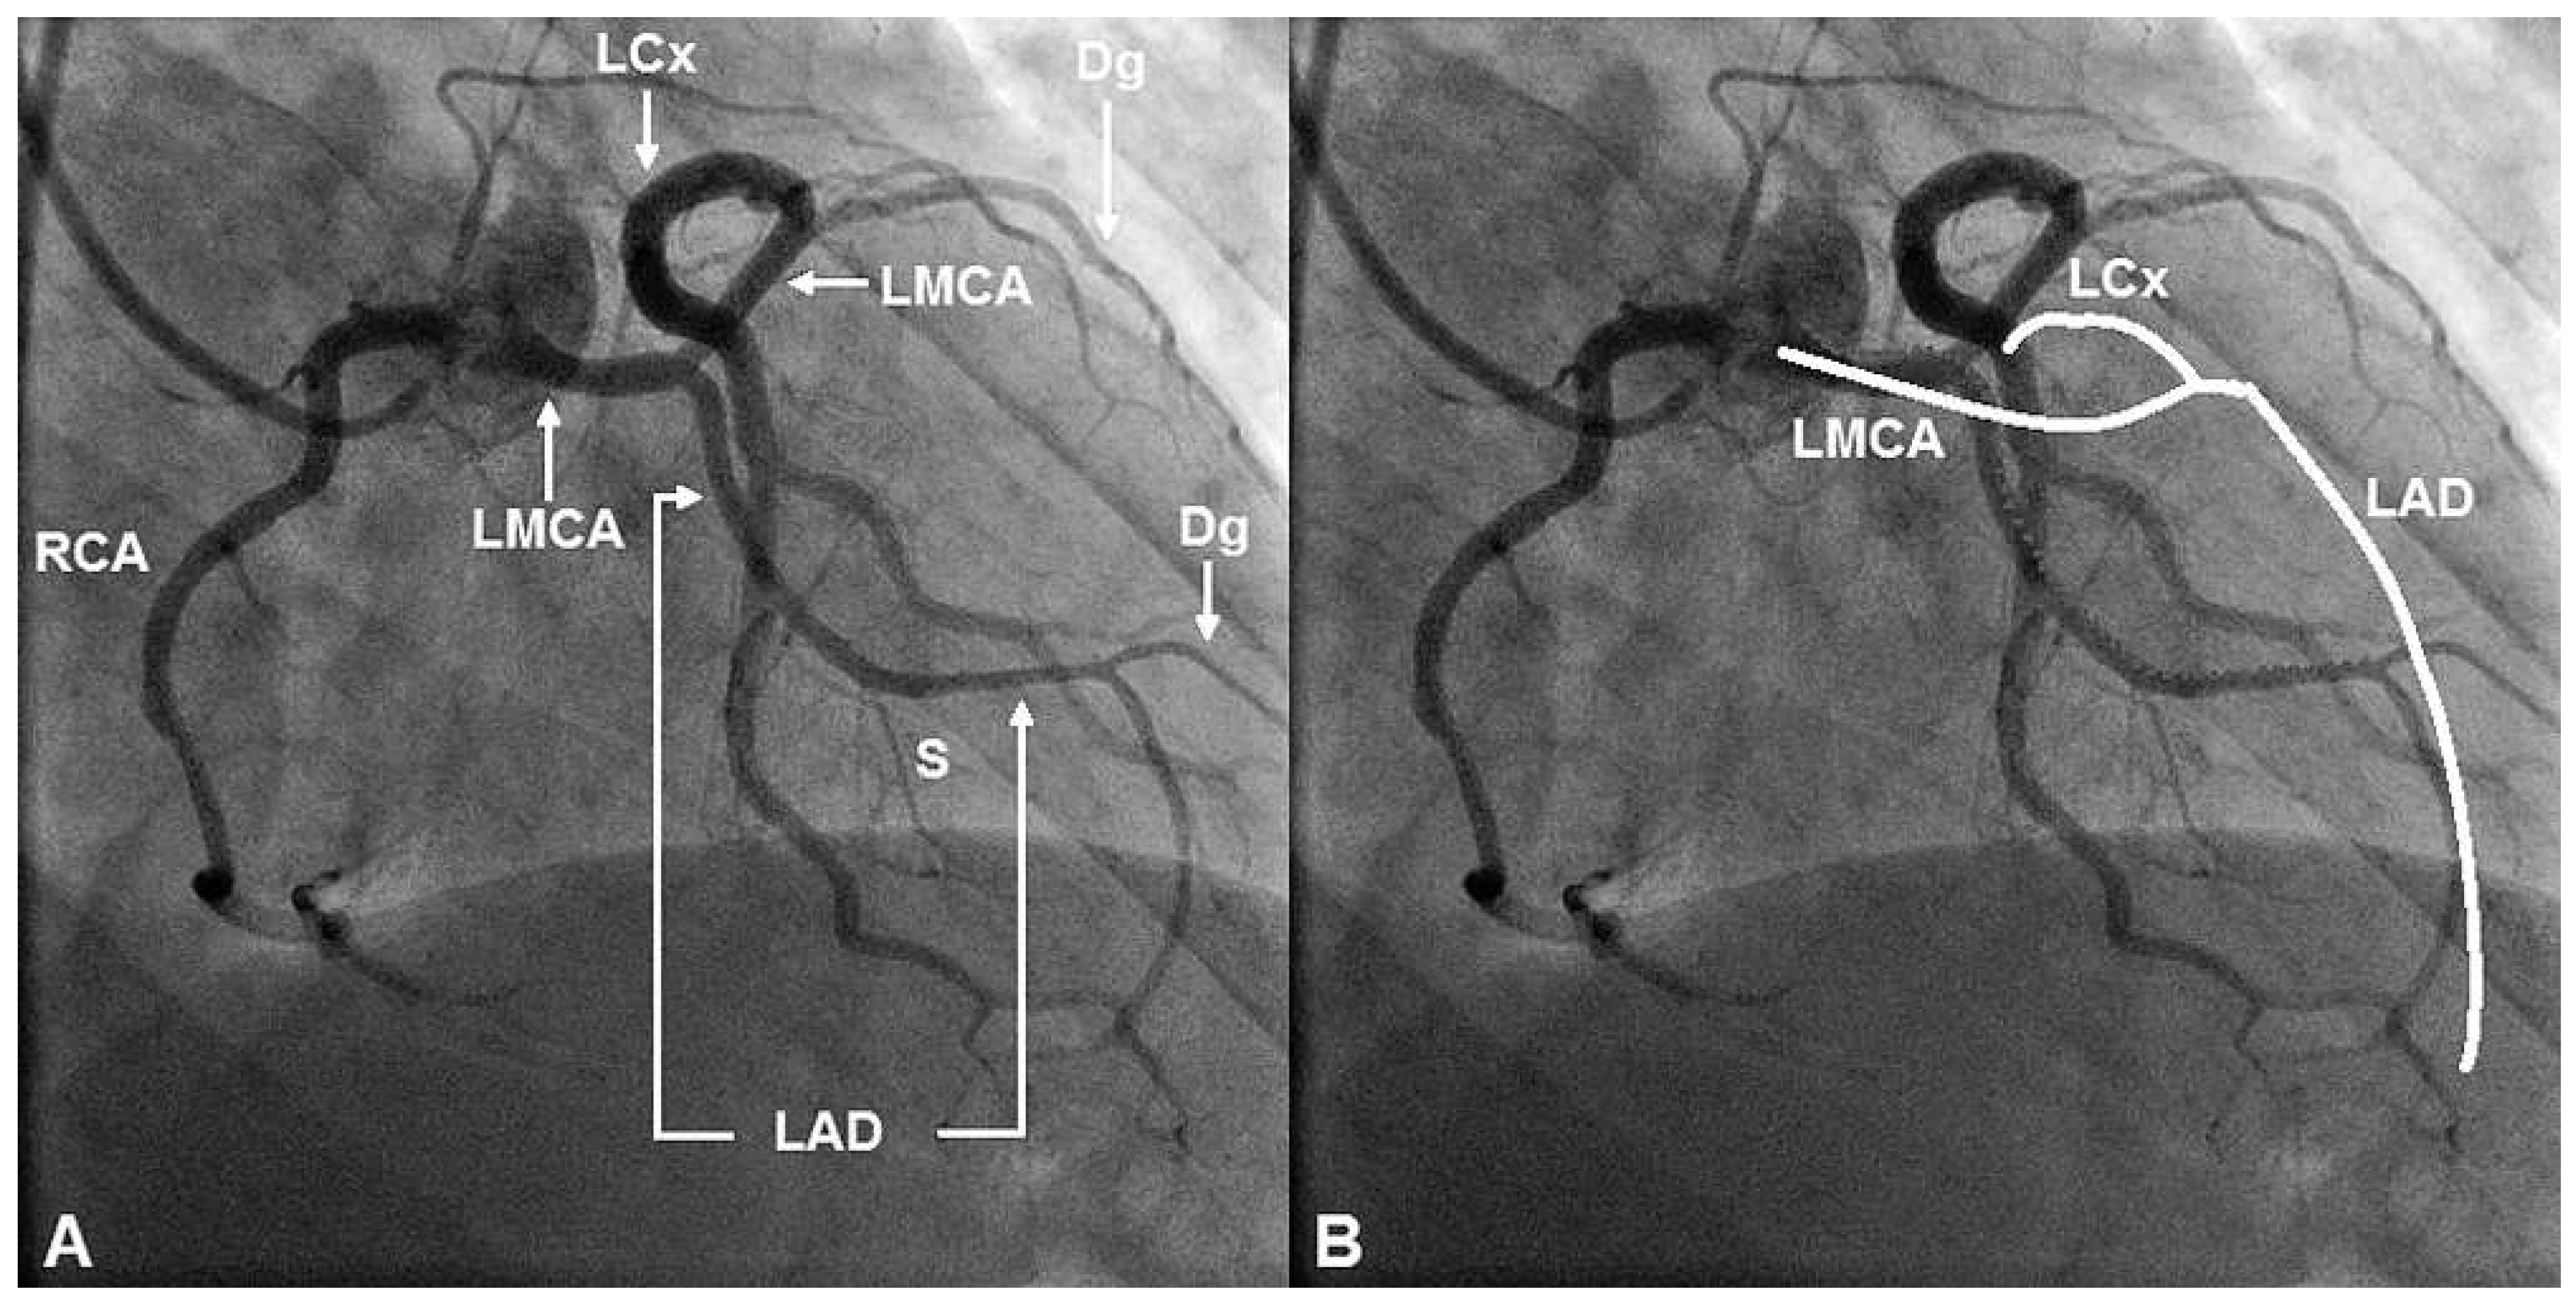

Case report

Discussion